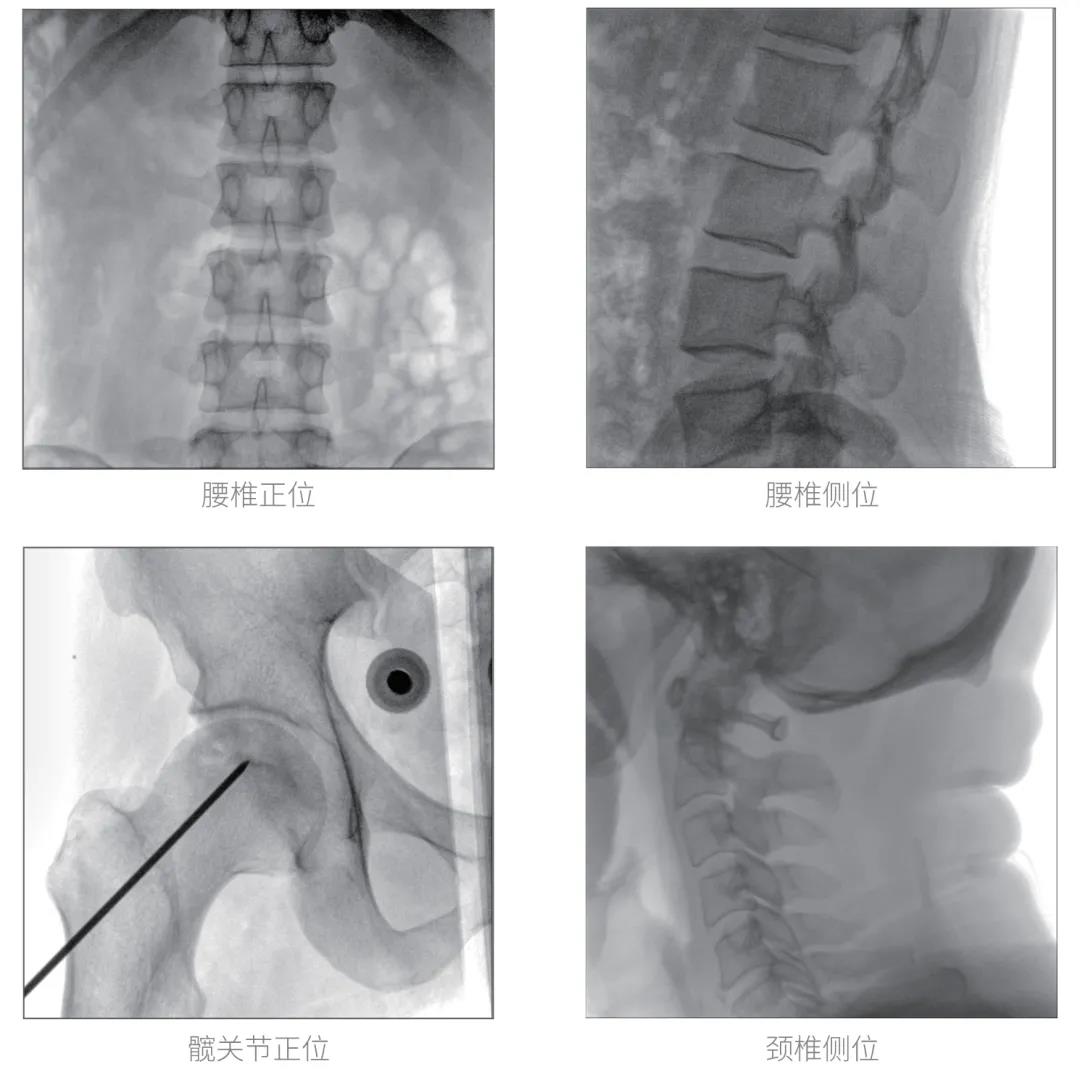

經過認真詳盡的設備審核驗收,“慧瞳”正式投入使用,普愛醫療一體化平板C形臂采取的動態平板探測器和智能圖像處理技術,讓臨床圖像更加清晰。

普愛醫療一體化平板C形臂“慧瞳”采用小巧緊湊的一體化機架設計,配合高性能的動態平板探測器,移動靈活,成像清晰,是各級醫院開展骨科及其相關外科手術的科室使用的理想設備。

智能化實時圖像處理技術,自動分析圖像并進行增強處理,減少臨床應用中處理圖像時的繁瑣操作,快速提供優質圖像方便完成臨床工作。

根據人體部位與射線劑量自動調整圖像幀頻,在保證圖像質量的同時降低射線劑量。